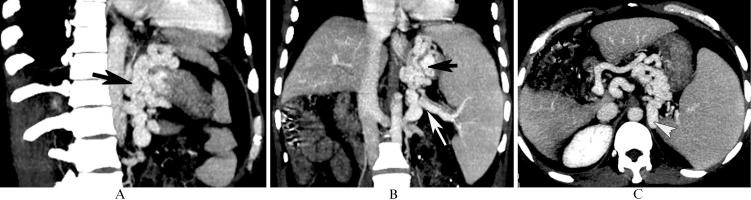

The aim of this study was to determine whether and how the diameter of the vein that gives rise to the inflowing vein of the esophageal and gastric fundic varices secondary to posthepatitic cirrhosis, as measured with multidetector-row computed tomography, could predict the varices and their patterns.

A total of 106 patients with posthepatitic cirrhosis underwent multidetector-row computed tomography. Patients with and without esophageal and gastric fundic varices were enrolled in Group 1 and Group 2, respectively. Group 1 was composed of Subgroup A, consisting of patients with varices, and Subgroup B consisted of patients with varices in combination with portal vein-inferior vena cava shunts. The diameters of the originating veins of veins entering the varices were reviewed and statistically analyzed.

The originating veins were the portal vein in 8% (6/75) of patients, the splenic vein in 65.3% (49/75) of patients, and both the portal and splenic veins in 26.7% (20/75) of patients. The splenic vein diameter in Group 1 was larger than that in Group 2, whereas no differences in portal vein diameters were found between groups. In Group 1, the splenic vein diameter in Subgroup A was larger than that in Subgroup B. A cut-off splenic vein diameter of 8.5 mm achieved a sensitivity of 83.3% and specificity of 58.1% for predicting the varices. For discrimination of the varices in combination with and without portal vein-inferior vena cava shunts, a cut-off diameter of 9.5 mm achieved a sensitivity of 66.7% and specificity of 60.0%.

The diameter of the splenic vein can be used to predict esophageal and gastric fundic varices and their patterns.